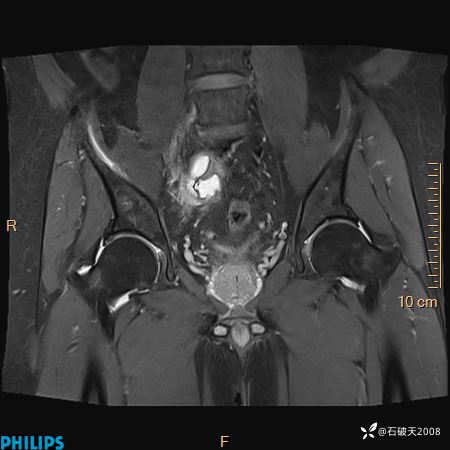

2023年3月份MRI影像

T2压脂冠状位